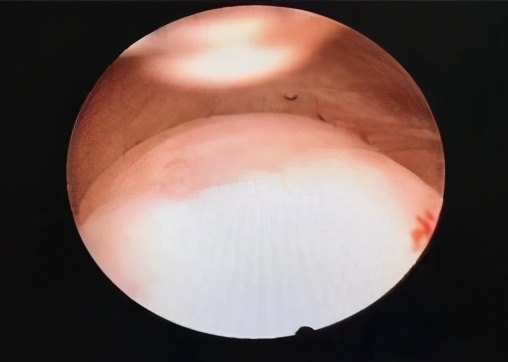

近日,科室收治了一名患者,该患者因月经淋漓不净伴阴道不规则流血,中度贫血,彩超提示宫腔内不均、质低回声团,大小约4.5x5.0cm大小。患者在外院就诊咨询后,建议行子宫全切,患者抱着保留子宫的愿望来到我院妇科,因患者肌瘤较大(一般宫腔镜下肌瘤挖除,建议肌瘤不超过3cm)。患者肌瘤较大,手术难度较高,但患者保留子宫的意愿非常强烈。结合患者基本情况,管床医生和科室业务⻣干反复讨论后拟定了患者的手术方案,于6月118日在静脉麻醉下完整进行了肌瘤摘除。手术时间短,创面小,术后基本无流血,病人恢复良好。